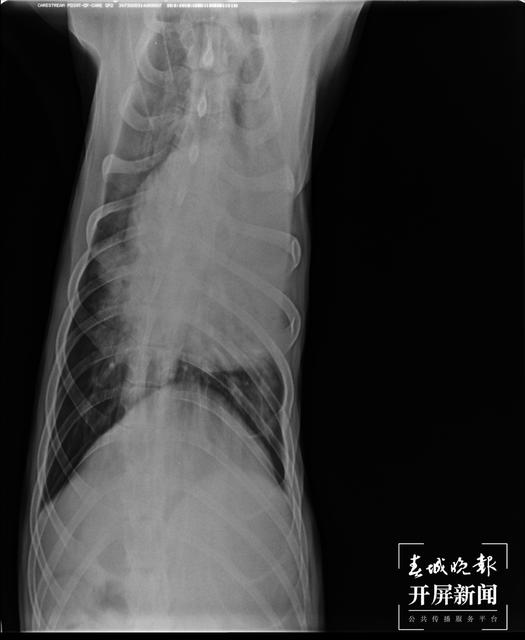

寄养期间,店主在2月8日至14日期间每天发一条视频反馈遛狗情况,但2月15日并未反馈,至2月16日反馈称有球虫,2月17日反馈称狗“这两天胃口不好、肠胃不好”,至18日语音通话告知“好像感冒了”。在领回时,杨女士发现宠物狗状态极其反常,遂立即送医,经医院诊断为感染肺炎、肺部严重水肿。

2月19日,CT显示肺部水肿严重。(受访者供图)